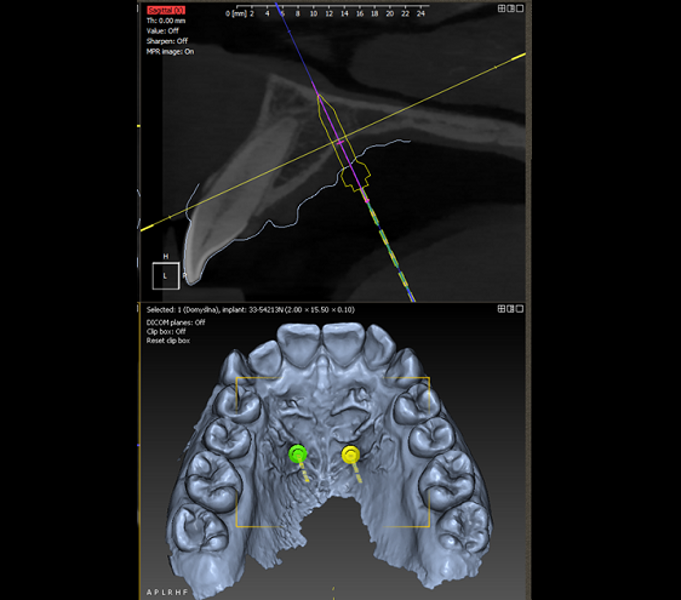

DDS-Pro enables precise planning, guided implantation and appliance design in orthodontics by integrating CBCT data and intra-oral scans into a streamlined digital workflow. (All images: Polorto)

1. capture and analysis of the CBCT scan and intra-oral scan to determine optimal mini-implant placement in line with anchorage needs and appliance design;

2. creation of surgical guides for precise implantation;

3. fabrication of the appliance for installation immediately after implantation; and

4. implantation and appliance installation using a 3D-printed guide.

DDS-Pro software (Polorto) supports both the two-stage and single-stage approaches. However, the single-stage method eliminates implant position discrepancies commonly encountered in the two-stage workflow. It also significantly enhances installation accuracy, improving reproducibility and eliminating the need for additional appointments or chairside adjustments.

Once 3D planning has been completed, mini-implants can be placed with high precision, independent of the operator’s manual skill. The appliance, anchored to these implants, functions exactly as designed.